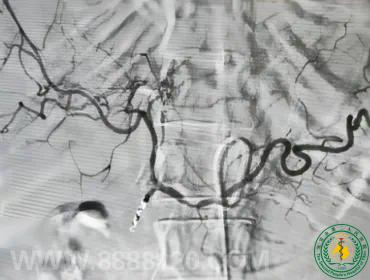

宜宾市第二人民医院 图文